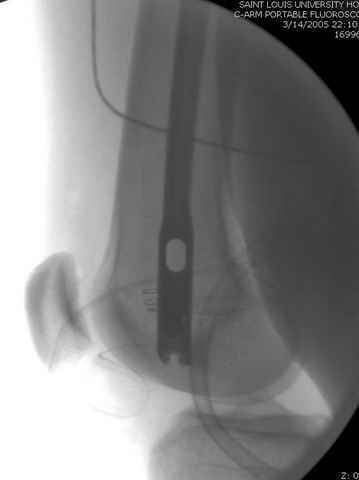

По поводу открытого перелома больной ургентно взят на ретроградное интрамедулярное штифтование, после рутинного дебрайдмента и фасциотомии на бедре и на голени.

перелом бедра

интраоперационные

постоперационные